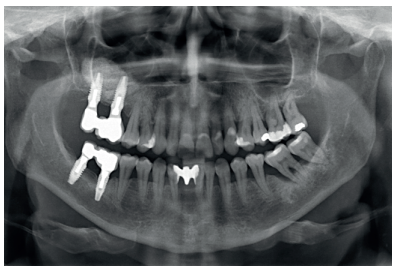

This was the case of a 58-year-old female patient who attended the dentist practice to assess the 16th and 17th molars for pain and mobility. On clinical examination, mobility of both was observed with suppuration at the level of the sulcus. Radiography confirmed our diagnosis of considerable bone loss and sinus perforation at the apex of both molars (Figure 2).